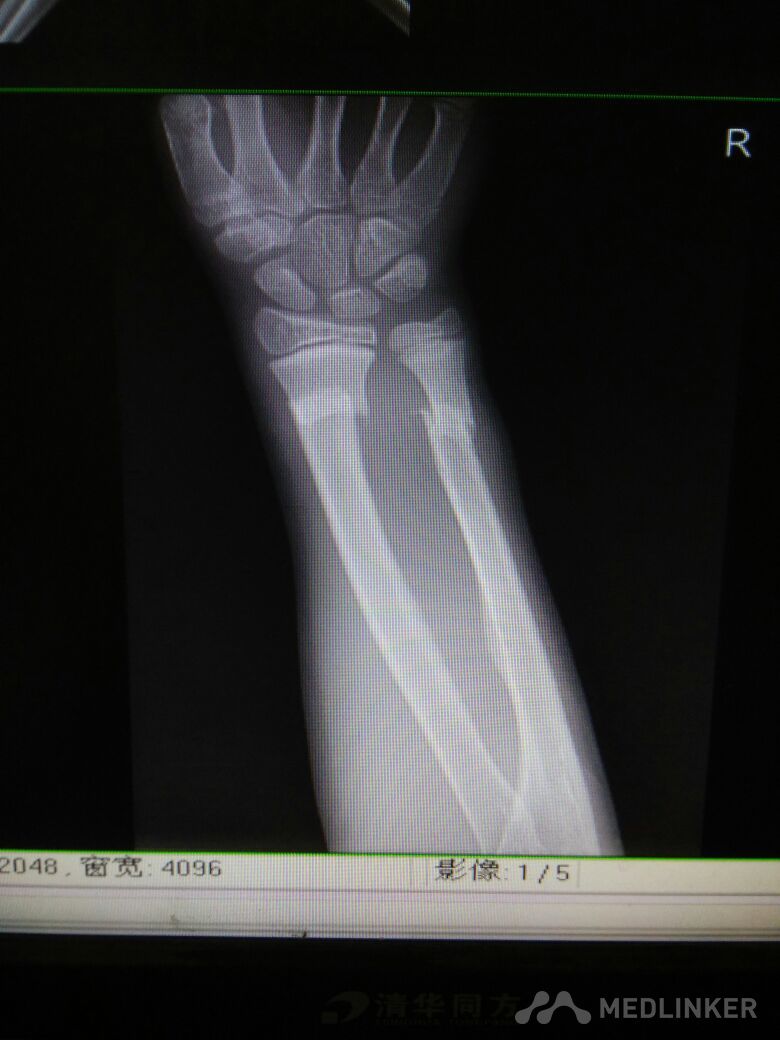

脾破裂,右尺桡骨骨折

尺桡骨骨折

病员男性,15岁。车祸伤致腹痛、右腕部畸形活动受限3小时入院,腹部B超提示:腹腔肠间隙积液,脾破裂。DR检查:右尺桡骨远端骨折。入院后行急诊剖腹探查术脾切除,右尺桡骨手法复位小夹板外固定,右腕复查对位久佳,这种还须手术切开复位吗?